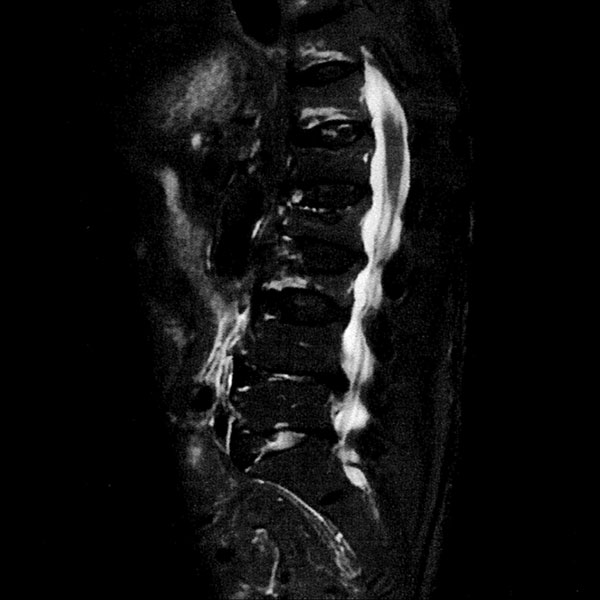

MRI検査

2025年9月16日スタート!!1.5T MRI SIGNA Creator(GE社製)

新しいMRI装置では従来の装置と比較し、高画質、かつ短時間での検査が可能となります。

- AI 機能を搭載:従来の装置と比べかなりの高画質が期待できます

- 従来の装置では難しかった微細な変化の描出にも期待がもてます

- PROPEELR 機能により、動きを抑えたきれいな画像が得られます